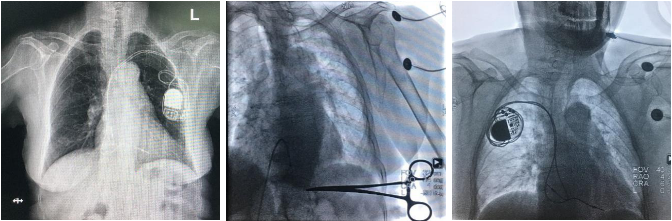

病人术前、成功拔除电极后以及重新在对侧植入起搏系统后的X影像